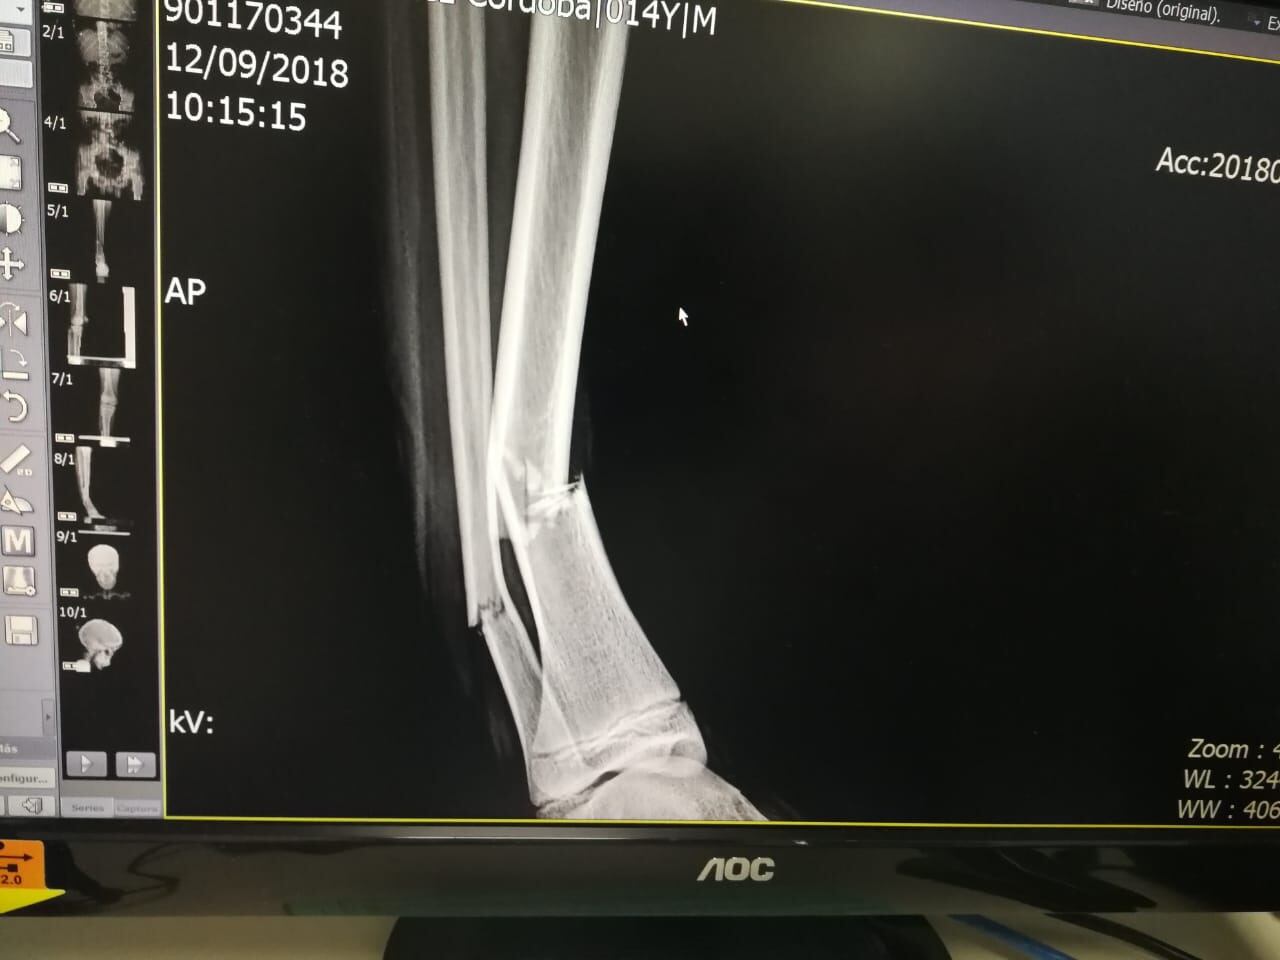

Córdoba dijo que a raíz del accidente Deyton sufrió tres fracturas en su pierna derecha y golpes en todo su cuerpo, especialmente en su cabeza, motivo por el cual tuvo que llevar un proceso de rehabilitación de más de tres meses.